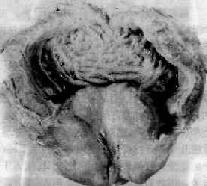

肉眼观,正常前列腺约栗子大,重约20g,增生的前列腺可达正常的2~4倍,甚至可达100g以上。切面见增生多发生于尿道两侧与后侧,或偶见只限于尿道后侧,将尿道压迫成一裂隙,并在膀胱的尿道开口处向膀胱内凸出(图14-2)。增大部的前列腺呈结节状,一般直径在0.5~2cm,灰白色,有纵横交错的条纹,其间夹杂有蜂窝状小孔,或小囊腔。切面的形态和增生的成分有关,如纤维、肌肉组织增生较显著时,则质地较实韧;如腺体增生较显著,则呈白色或灰黄色蜂窝状或囊性结构,用手指压迫时可有较多白色混浊的分泌物溢出于切面上。增生周围的前列腺组织被压迫而形成一假性包膜,所以能将增生的结节剥离出来。

图14-2 前列腺增生症

前列腺明显肿大,压迫膀胱颈部,且部分突入膀胱三角区;膀胱扩张肥厚,粘膜面可见代偿肥大的平滑肌条索呈梁状